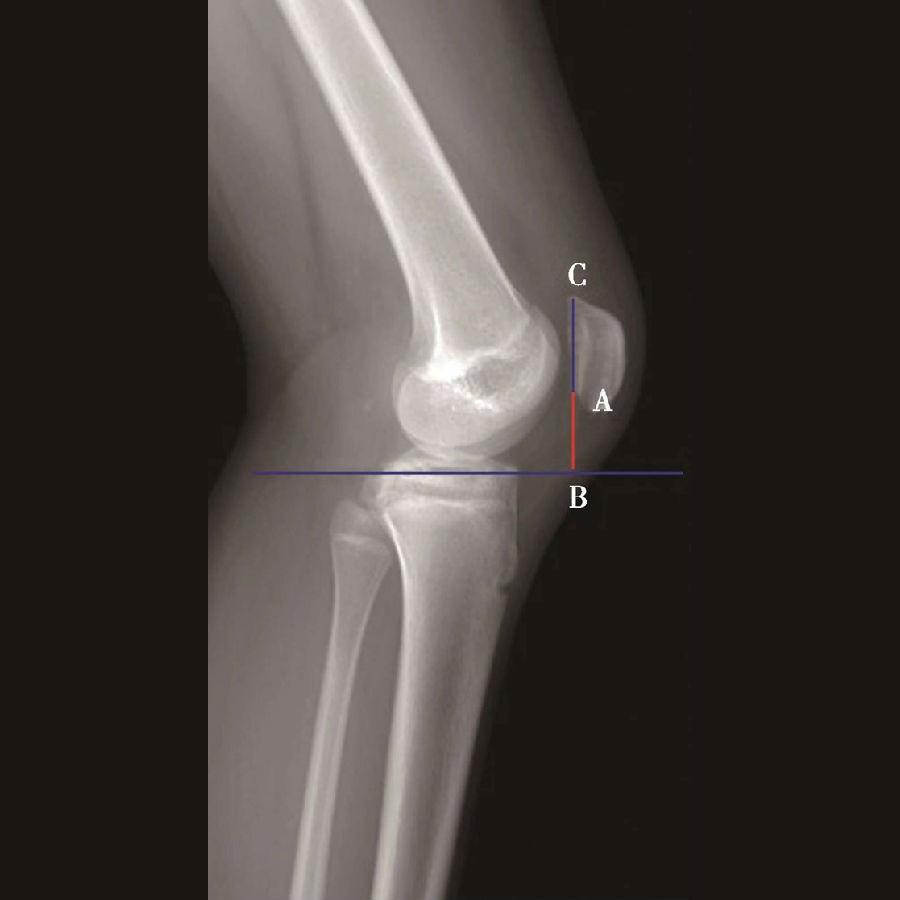

3️⃣ BlackBurne-Peel指数>1.0提示高位髌骨(图8),<0.5提示低位髌骨(图9)。

体位:侧卧位,屈膝无要求。

如图示:AB是髌骨关节面最低点到胫骨平台延长线的垂直距离。AC是髌骨关节面的长度。BlackBurne-Peel指数=AB/AC(图7)。

该方法同样可以评估胫骨结节移位或胫骨高位截骨术后的髌骨高度。但是也有其缺点:①部分患者的髌骨形态异常,难以分辨髌骨关节面的长度;②标记胫骨平台的延长线也需要较高的精度;③胫骨平台后倾角越大,可能导致髌骨关节面的最低点到胫骨平台的延长线的垂直距离越短。因此,如果手术改变了胫骨平台的后倾角度,则会使BlackBurne-Peel指数出现偏差。

图7 BlackBurne-Peel指数=AB/AC=0.80,为正常髌骨高度

图8 BlackBurne-Peel指数=AB/AC=1.20,为高位髌骨

图9 BlackBurne-Peel指数=AB/AC=0.49,为低位髌骨